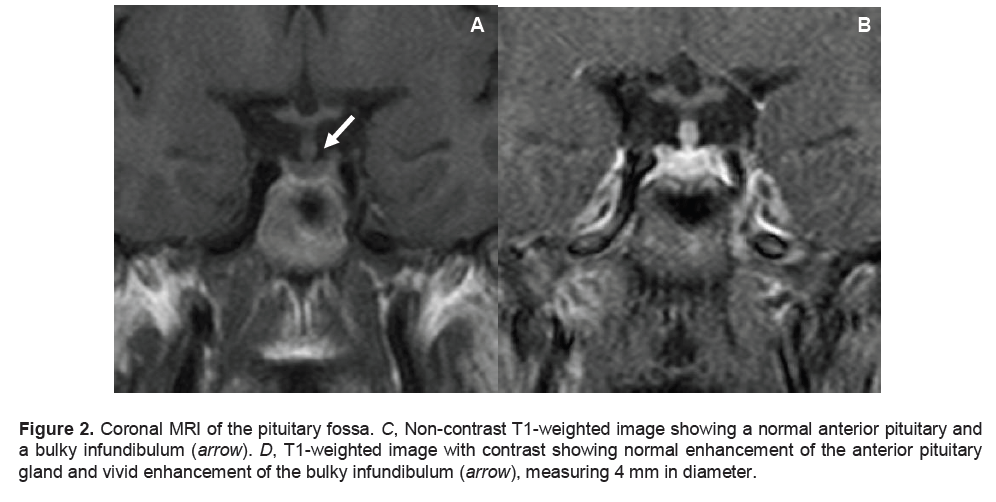

The results of the water deprivation test confirmed the diagnosis of central diabetes insipidus. At a serum osmolality of 303 mmol/kg, urine osmolality remained low at 71 mmol/kg. After desmopressin 2 μg was given subcutaneously, serum osmolality decreased to 286mmol/kg and urine osmolality increased to 611 mmol/kg (Table 2). Skull radiograph was unremarkable. A Magnetic Resonance Imaging (MRI) of the pituitary fossa revealed a normal anterior hypophysis, with a small (4 mm x 2 mm) nodular enhancing appearance of the lower part of the pituitary infundibulum associated with ectopia of the posterior pituitary gland, compatible with infundibuloneurohypophysitis (Figures 1 and 2).

Figure 2. Coronal MRI of the pituitary fossa. C, Non-contrast T1-weighted image showing a normal anterior pituitary and a bulky infundibulum (arrow). D, T1-weighted image with contrast showing normal enhancement of the anterior pituitary gland and vivid enhancement of the bulky infundibulum (arrow), measuring 4 mm in diameter.

There are more definite radiological features in LINH. These include characteristic diffuse thickening of the pituitary stalk, with a greater diameter exceeding 3.5 mm at the level of the median eminence of the hypothalamus.2,6 On MRI, the normal smooth tapering of the infundibular stalk is lost and there are varying degrees of asymmetry. A common finding is marked gadolinium enhancement of the stalk, extending into the lower hypothalamus. 2,6 Loss of the usual neurohypophyseal bright spot on MRI T1-weighted images is commonly reported, which has been shown to correlate closely with a loss of function of the neurohypophysis.7,8 The cases reported exhibited loss of the neurohypophyseal bright spot; but those with less than two years duration of diabetes insipidus had thickened pituitary stalk, enlarged neurohypophysis, or both, which subsequently disappeared on follow-up imaging.9 Additionally, the anterior pituitary is usually of normal size and signal intensity. There are some reported cases presenting with swelling of the whole pituitary gland and stalk with no appreciable anterior pituitary dysfunction. In our patient, non-contrast T1-weighted images revealed the absence of the usual bright signal of the posterior pituitary gland, a normal anterior pituitary and a bulky infundibulum. There was normal contrast enhancement of the anterior pituitary gland and vivid enhancement of the bulky infundibulum (Figures 1 and 2).